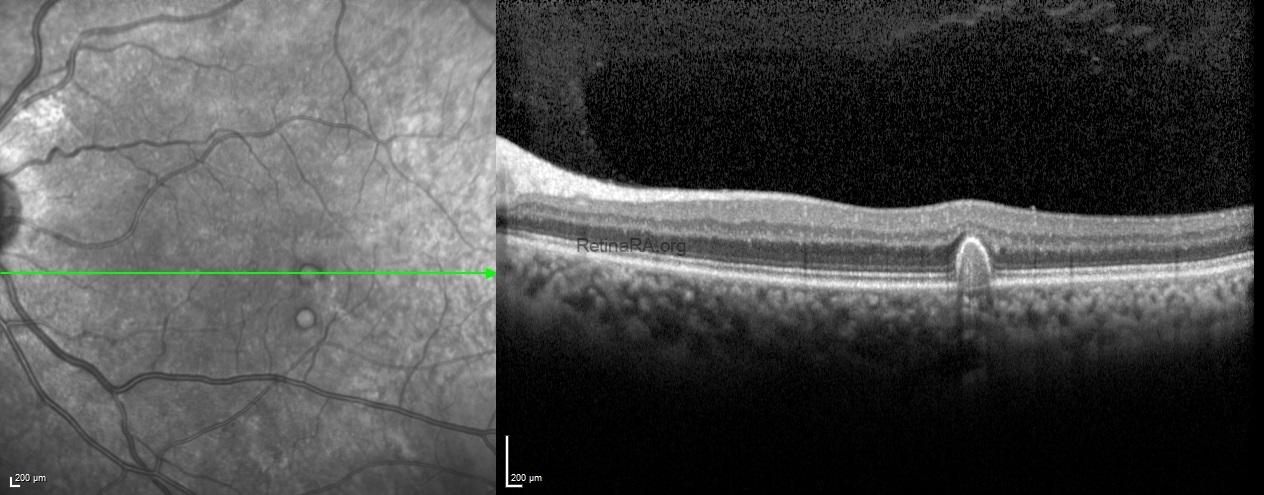

Fundus images of both eyes showed diabetic microaneurysms and a few yellow large drusen (

>125 μm) in the macula.

Spectral-domain optical tomography scans passing through the drusen demonstrated the dome-shaped retinal pigment epithelial elevations with variable internal reflectivity of drusen.